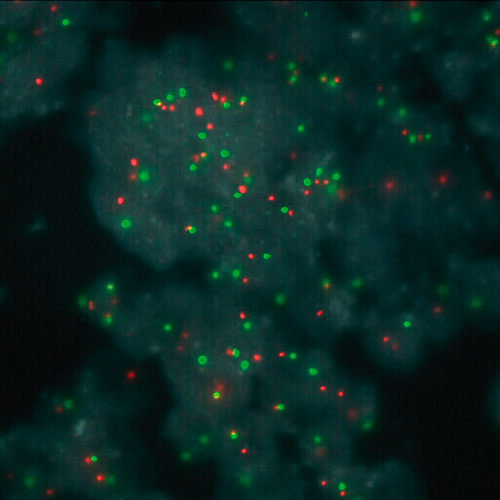

FUS (16p11) Break probe hybridized to liposarcoma material.

The fused in sarcoma (FUS) gene was originally shown to be rearranged in myxoid liposarcomas harboring a t(12;16)(q13;p11) translocation. FUS has also been shown to be involved in other recombinations: with ERG in acute myeloid leukemia carrying a t(16;21), with ATF1 in band 12q13 in angiomatoid fibrous histiocytoma, and with CREB3L2 in fibromyxoid sarcoma. A break or split probe for FUS is best used to analyze translocation of the FUS (16p11) gene on formalin fixed paraffin embedded tissue for routine clinical diagnosis. The FUS (16p11) Break probe is optimized to detect translocations involving the FUS gene region at 16p11 in a dual-color, split assay on metaphase/interphase spreads and paraffin embedded tissue sections.